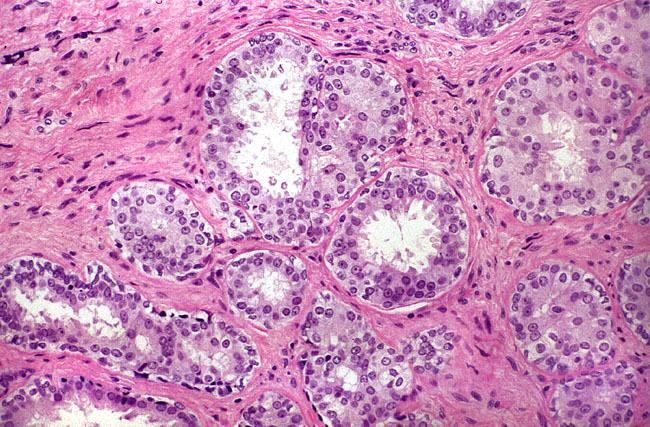

Исследование: микропрепарат молочной железы в медицине

Раздел: Снимки-откровения